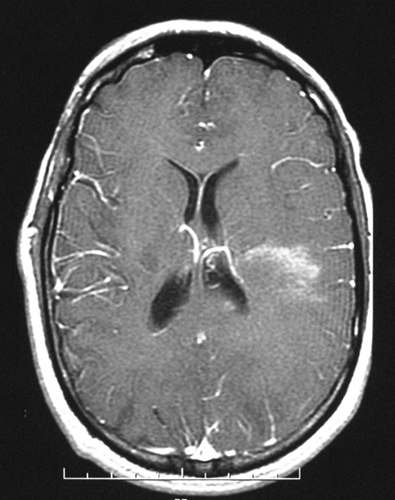

The FLAIR sequences (Panel A) demonstrate an extensive abnormality with increased intensity signal and irregular borders that involves the left occipital, parietal and dorsal frontal lobes. Although the lesion is quite extensive the mass effect is minimal. On the post contrast T1-weighted sequences (Panel B) there is enhancement only in the anterior border of the lesion. The limited mass effect along with the “crescent” rim enhancement are suggestive of  demyelinating process, likely tumefactive multiple sclerosis.